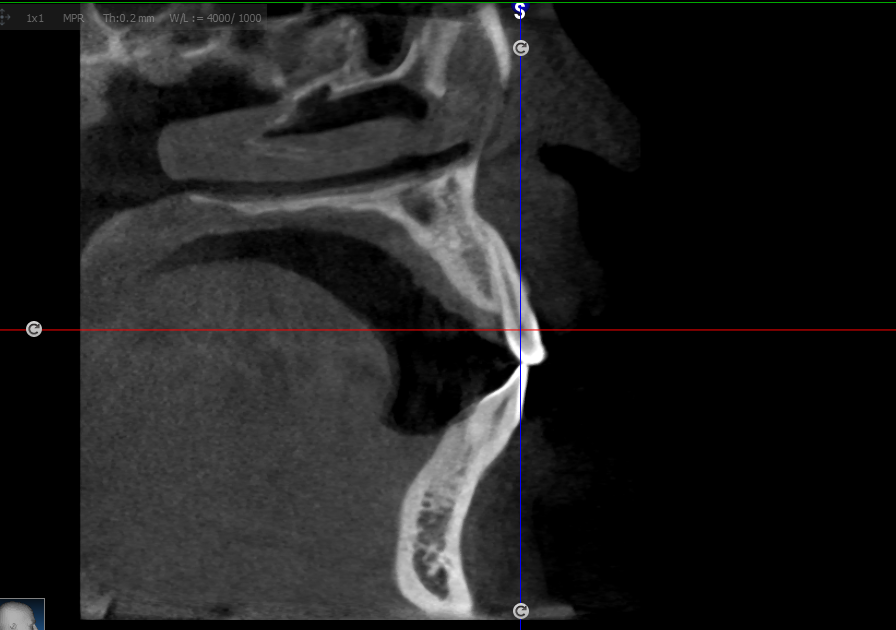

CBCT pada Penatalaksanaan Cleft Lip and Palate (Bibir Sumbing)

Bone graft sering digunakan dalam kedokteran gigi maksilofasial untuk memperbaiki defek tulang setelah kejadian seperti kista, trauma, tumor, atau kehilangan gigi. Keberhasilan graft sangat dipengaruhi

Fibrous dysplasia adalah kelainan jaringan tulang jinak di mana jaringan fibrosa menggantikan jaringan tulang normal, mengakibatkan deformitas, penebalan tulang, dan perubahan fungsi. Di daerah maksilofasial,